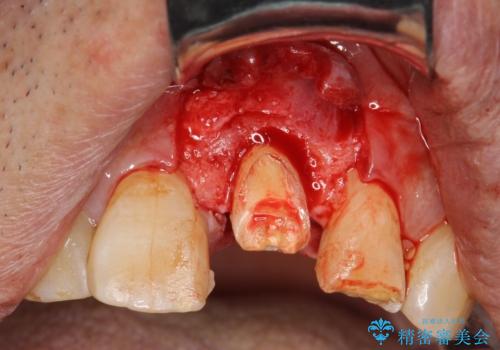

根管治療をした上で歯を引っ張りだして(エクストリュージョン)、その後、骨外科にて歯周組織を整えた上で、かぶせものを入れていく治療計画をたてました。

歯を引っ張りあげたり、手術をしたあとの治り待ちをしたり、治療に時間がかかる方法ではありましたが、抜かずにその歯を使うことができたことで、患者さんにはとても満足していただけています。